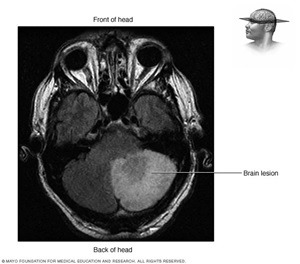

Brain Lesion

A brain lesion is an abnormality seen on a brain imaging test, such as an MRI or CT scan. A brain lesion may involve small to large areas of your brain, and the severity of the underlying condition may range from relatively minor to life-threatening.

A brain lesion usually is discovered during an imaging test for an unrelated condition or symptom. Concussions and lesions are not the same thing. Concussions more often occur without ever causing any changes on the CT or MRI images, and are diagnosed by symptoms and not imaging tests.